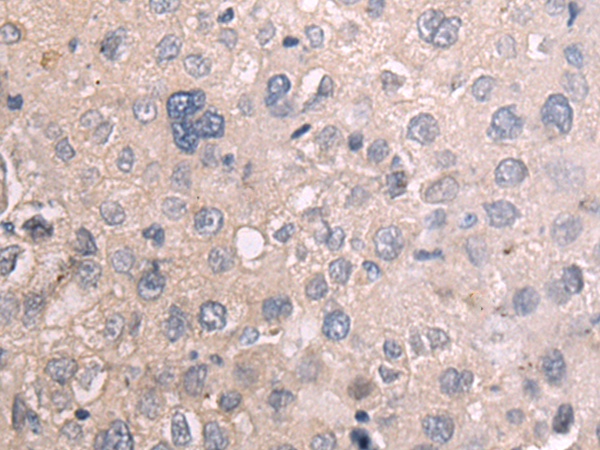

分类: 科研抗体货号: P11132别名: MAP-2; Mtap2; Mtap-2应用: IHC反应种属: Human, Mouse, Rat